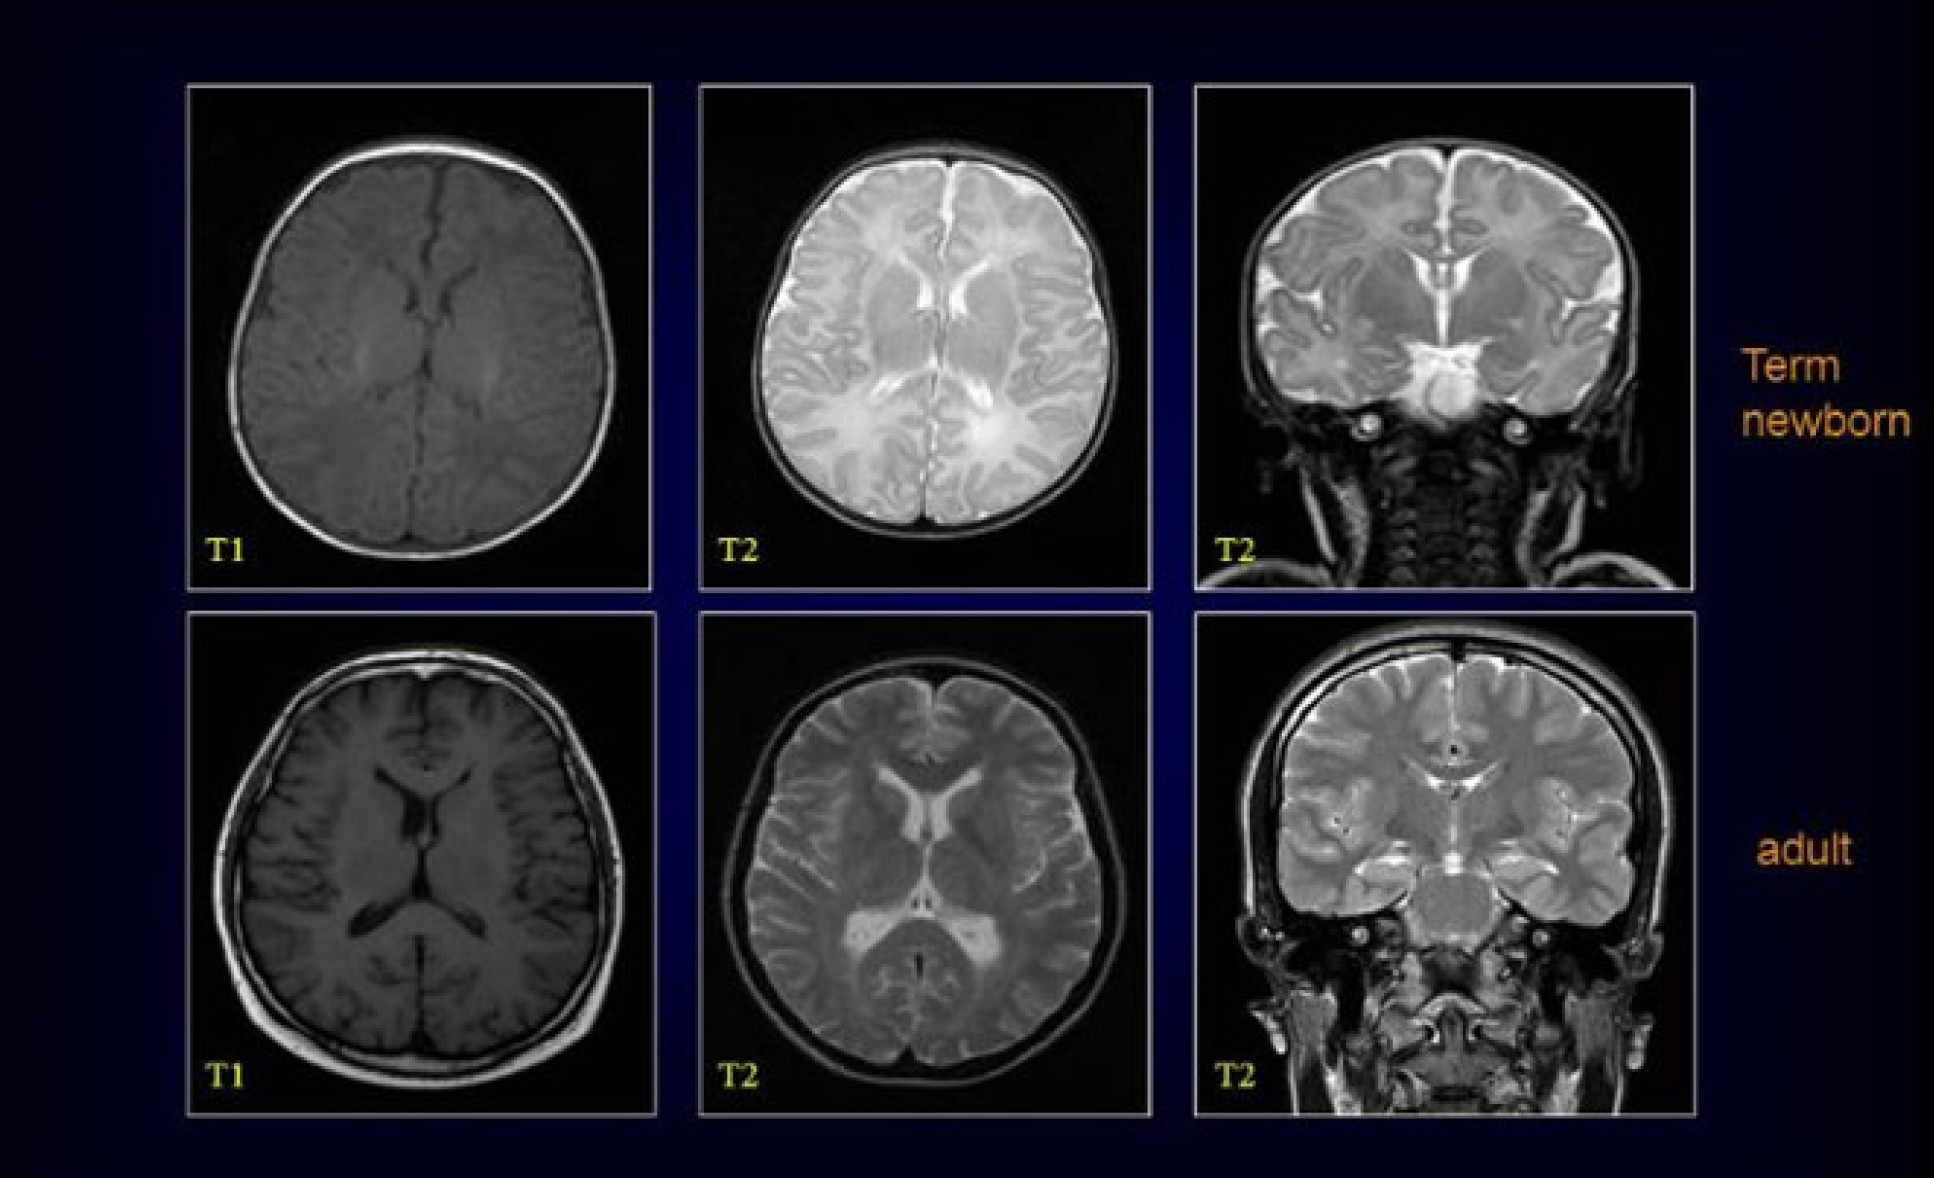

Air pollution is likely to affect the placenta and prenatal and postnatal neurodevelopment. However, it is unclear at this stage whether placental function is impaired by air pollution, and whether this leads to further adverse health outcomes in the mother and baby. Further, the evidence on neurodevelopmental effects of prenatal exposure to air pollution comes mostly from epidemiological studies and very little personal exposure work has been undertaken. Perinatal brain magnetic resonance imaging (MRI) offers the opportunity to assess the impact of prenatal exposure to air pollution on brain development. To date, as far as I’m aware, no such studies have been conducted. The aim of this PhD project is to understand how exposure to air pollutants impacts prenatal neurodevelopment.

To achieve these objectives, maternal air pollution exposure for a healthy, term-born cohort and a preterm cohort will be modelled. The subjects in these cohorts underwent MRI in the neonatal period, and any effects of maternal air pollution exposure during pregnancy on the brain will be assessed. Preterm babies are of concern, as while they may have been exposed prenatally for a shorter period, they are more vulnerable to neurodevelopmental impairment.

The mechanism of impacts on neonatal neurodevelopment due to prenatal exposure to air pollution is unclear. As described in the introduction, placental function may be impaired due to high maternal exposure to air pollution during pregnancy. I will investigate this link further by modelling prenatal exposure to air pollution and linking this with established placental T2* MRI datasets that will enable indices of placental oxygenation (a surrogate measure of placental function) to be assessed.